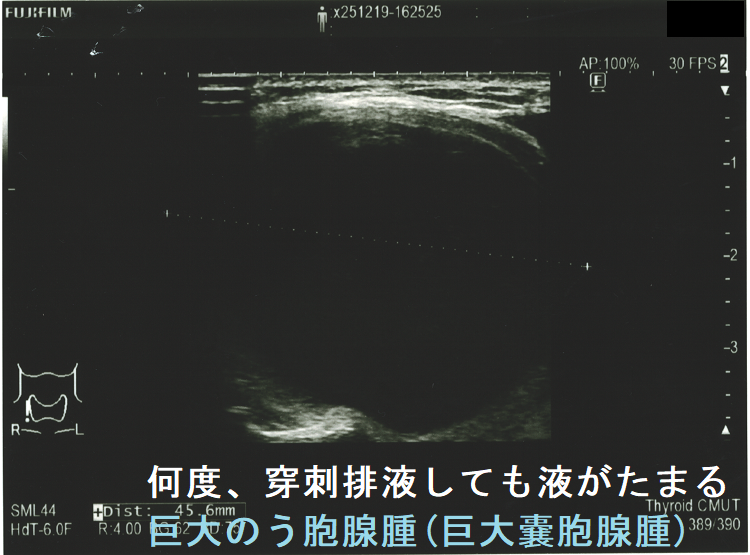

巨大のう胞腺腫(巨大嚢胞腺腫)もしくは通常サイズのう胞腺腫(嚢胞腺腫)が、

には、穿刺排液を行います。しかし、のう胞(嚢胞)中の液体は粘稠なため、通常穿刺針での排液は困難(すぐに詰まってしまう)。太い針でも完全に抜けない事が多い。18G(ゲージ)[輸血用の太い針]を使えば、ほとんどのケースで穿刺排液可能ですが、刺し口から出血して緊急入院になったケースが複数ありました(穿刺時出血)(それ以降、18Gは使用禁止にしました)。18G(ゲージ)でも無理なら、どうしようもありません(海外では16Gの極太針を使用する所もあるようですが・・・)(AJR Am J Roentgenol. 2008 Dec;191(6):1730-3.)。それ以来、無理して太い針を使用せず、抜けない場合は潔く諦めて内分泌外科に甲状腺部分切除(半葉切除が多い)を依頼します。

手術すべきか迷う巨大甲状腺のう胞腺腫(巨大甲状腺嚢胞腺腫)。横径 5.49cmで、ほぼ6cm。80歳以上なら全身麻酔のリスクを冒してまで手術しなくて良いかもしれません。せいぜい次項の経皮的エタノール注入療法(PEIT)ぐらいでしょう。

頻回に穿刺排液しても液がたまる巨大のう胞腺腫(巨大嚢胞腺腫)は、良性腫瘍(のう胞型濾胞腺腫:嚢胞型濾胞腺腫)であっても手術適応になります。単に、のう胞(嚢胞)と呼ばれる事も多いですが、甲状腺組織の破壊・変性によるのう胞変性(嚢胞変性)でなく、れっきとした腫瘍です。

(岩手県立中央病院の報告) 97 x 71 x 60 mmの巨大な甲状腺のう胞腺腫(甲状腺嚢胞腺腫)で、排液後1週間以内に液が再貯留し始めたため、甲状腺半葉切除したそうです。病理標本を確認すると、のう胞周囲は炎症が強く、炎症性浸出液の可能性が考えられました。(第57回 日本甲状腺学会 P2-070 巨大な甲状腺嚢胞により経口摂取困難となった一例)